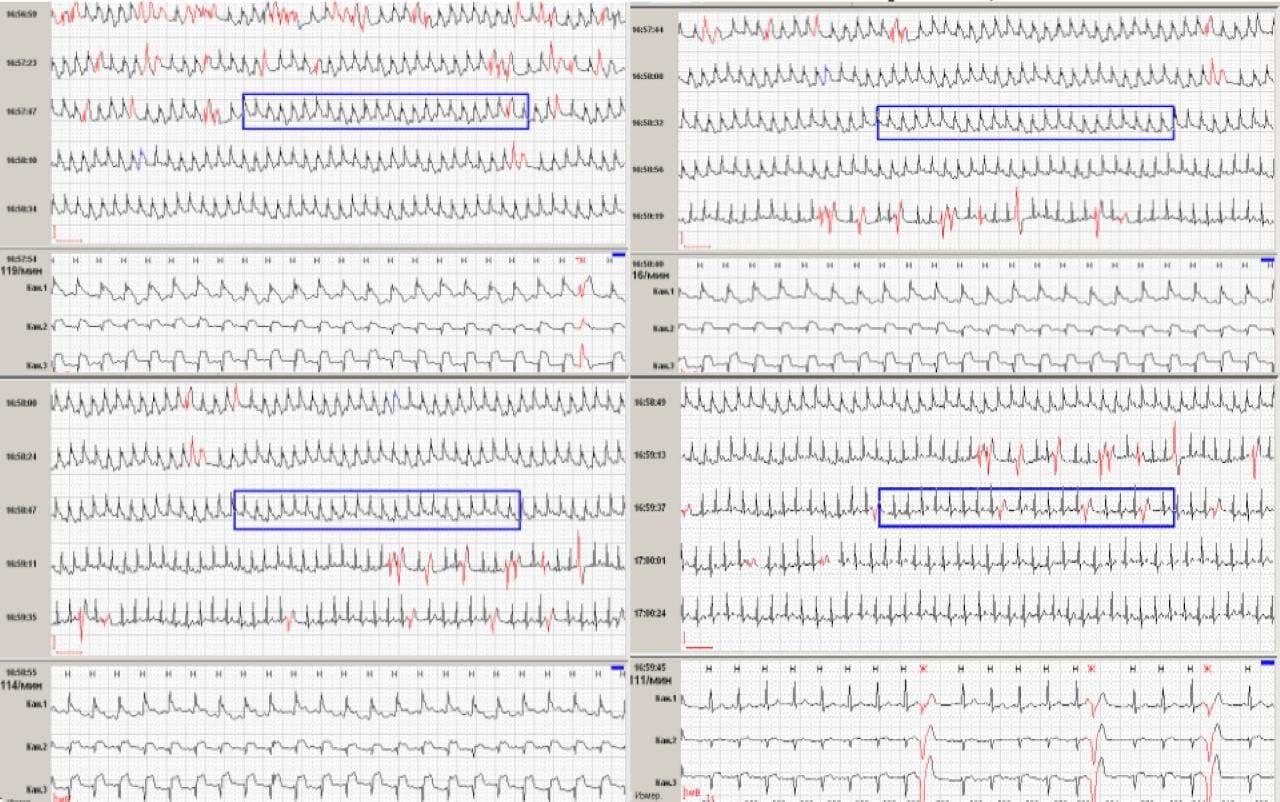

Аппарат ХМ чуть не потеряли...

Ecg electrocardiography / ЭКГ электрокардиография

Ночью не спала. Загрудинные боли. Вызвали СМП...

Удалось найти в соседней больнице...

Дневной Принцметал с ЖТ

Дневной Принцметал с ЖТ - пишет о нагрузке и перебоях. Жалоб на боль не было